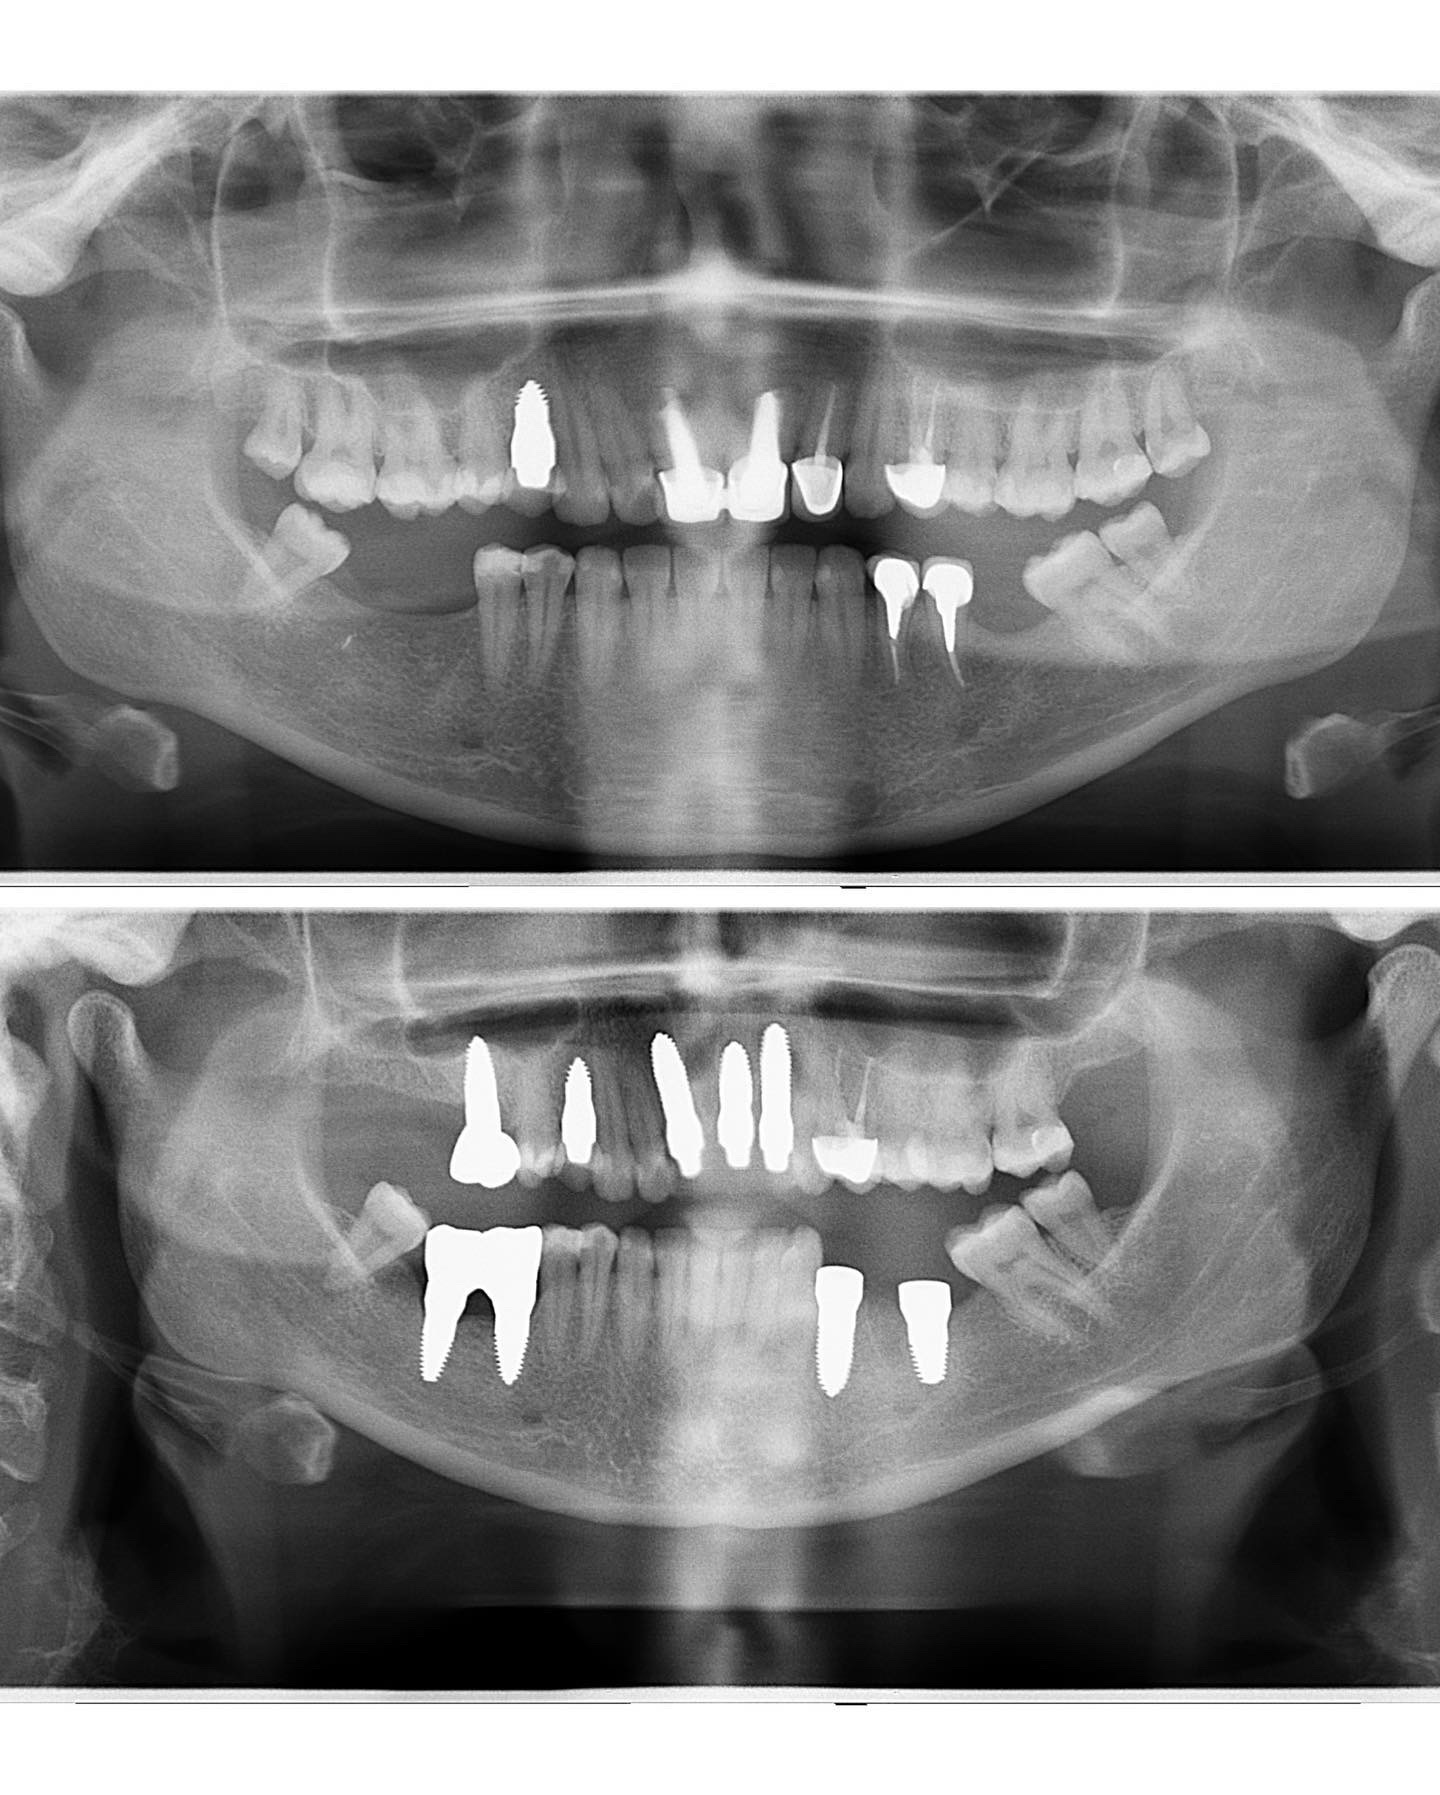

This connection was shown again with our patient in whom, due to tooth damage at a young age, after the previous removal of three nerves on the front teeth, coatings were installed. However, when we removed the veneers and removed the teeth, we detected very black roots that indicate completely rotten teeth.

The patient immediately had three @swissdentalsolutions ceramic implants placed and provisional crowns on top of these. During the procedure, when the teeth were removed, the patient already felt relief.